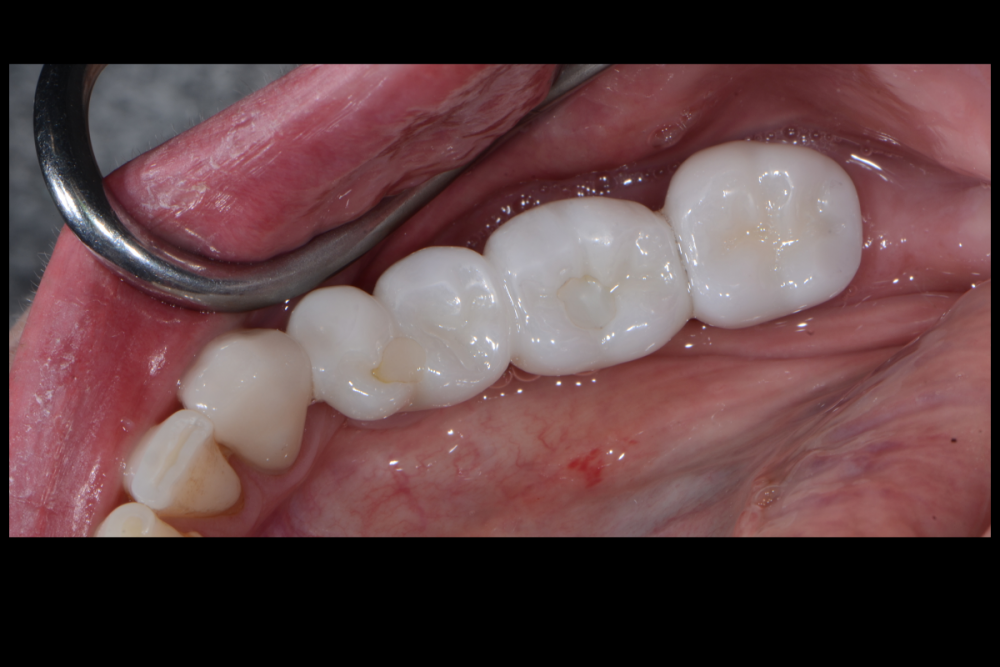

Карен Аванесов Опубликовано 11 февраля, 2022 Поделиться Опубликовано 11 февраля, 2022 все на слайдах. 2 Ссылка на комментарий

Карен Аванесов Опубликовано 12 февраля, 2022 Автор Поделиться Опубликовано 12 февраля, 2022 15 часов назад, АнтонТЛТ сказал: Я при таких сюрпризах делаю мобилизацию язычного лоскута, вестибулярный не мобилизирую, фдм вторым этапом. Что на 4 слайде справа? Делал и так ка ты написал. коллаген 15 часов назад, Irouil сказал: Кажется, там какой-то алографт на который сверху подсыпан ксено можно ли проследить вывод из работы, что лучше «без», чем «с»? Именно! и не только. Полезно смотреть старые работы. только не все пациенты исправно приходят Ссылка на комментарий

Карен Аванесов Опубликовано 15 февраля, 2022 Автор Поделиться Опубликовано 15 февраля, 2022 13.02.2022 в 22:56, Fin сказал: Карен. Подскажите пожалуйста. Правильно ли я понял, что в на данный момент в такой ситуации (оголение импланта с вестибулярной стороны на половину) Вы бы обошлись просто установкой импланта + ССТ вестибулярно? Да, именно так. 14.02.2022 в 10:33, Bier сказал: от подобной присыпки толку обычно нет. Олег, помнишь аник "темно здесь..." Вот только не начинай про полужесткие сосиски)))) Но ты прав или делпать по отработанной технологии или никак 1 Ссылка на комментарий

Карен Аванесов Опубликовано 15 февраля, 2022 Автор Поделиться Опубликовано 15 февраля, 2022 13.02.2022 в 22:56, Fin сказал: Карен. Подскажите пожалуйста. Правильно ли я понял, что в на данный момент в такой ситуации (оголение импланта с вестибулярной стороны на половину) Вы бы обошлись просто установкой импланта + ССТ вестибулярно? Это как вариант не на каждый случай конечно , но когда по делу все работает. Ссылка на комментарий